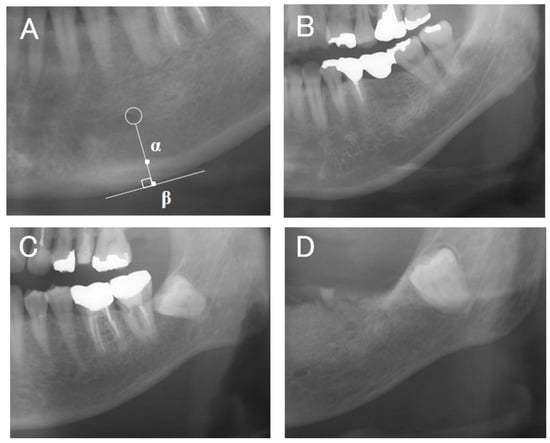

2.4. Measurement of Mandibular Cortical Width (MCW)

The cortical bone thickness (α–β) of the mandibular inferior cortex just below the mental foramen was measured by one examiner (K.S.) in increments of 0.1 mm three times on each side using the image analysis software described above (Figure 2A). The average of all measurements on both sides was taken as the representative value of the MCW.

2.5. Measurement of MCI

The morphology of the mandibular inferior cortex was classified into three types, as described by Taguchi et al. [9] (type 1, smooth inner surface of cortical bone; type 2, irregular inner surface of cortical bone with linear resorption; type 3, severe linear resorption and cortical bone rupture over the entire cortical bone) (Figure 2B–D). Evaluation was performed bilaterally, and the worst assessment was used. Diffuse opacities such as sclerosing osteomyelitis that did not correspond to any of the above types were recorded separately. MCI was assessed twice each by two dentists (K.S., a periodontist, and M.Y., a dental trainee) who were trained in classification beforehand, and the second assessment was used. The results of the two examiners were then compared; in the case of the same rating, the same rating was adopted, and in the case of a difference, the more severe rating was used as the final MCI value.

Figure 2. (A) The mandibular cortical width (MCW) was determined by drawing a perpendicular line from the mental foramen (circle) to the inferior margin of the mandible and measuring the distance between α and β. (B) Typical example of type 1 (normal category). (C) Typical example of type 2. (D) Typical example of type 3 (types 2 and 3 are the severe category).